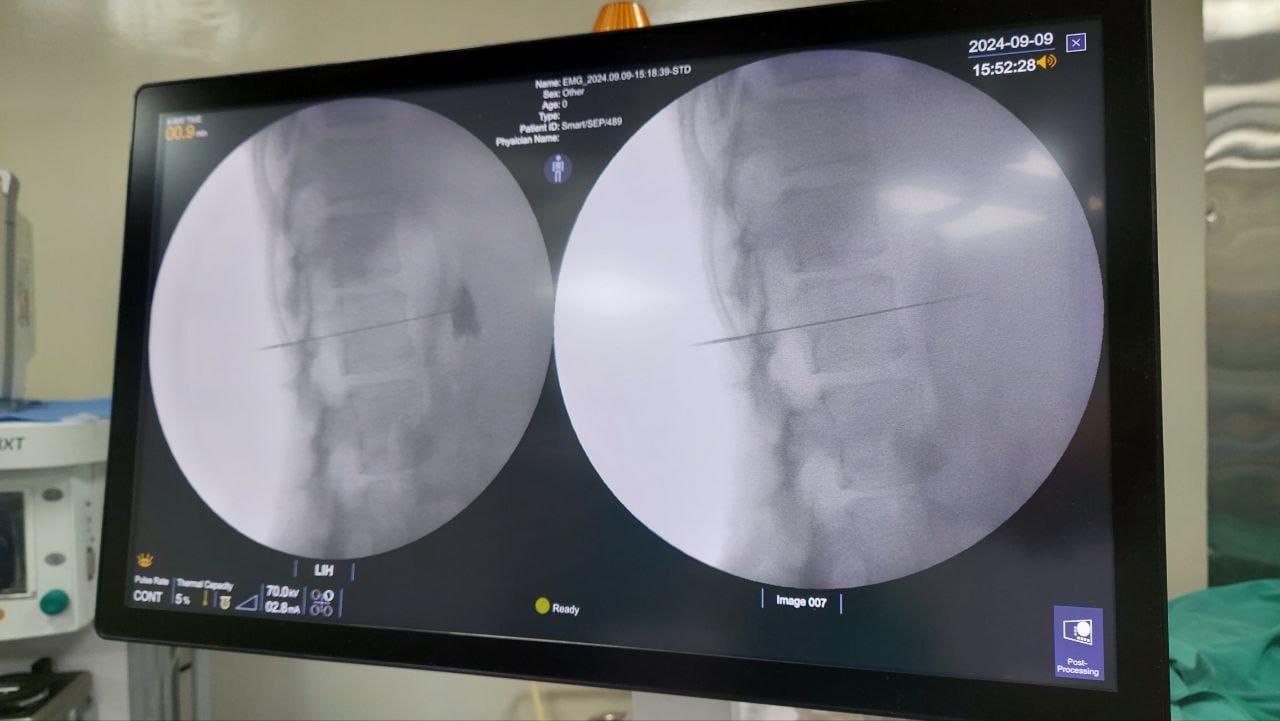

Procedures